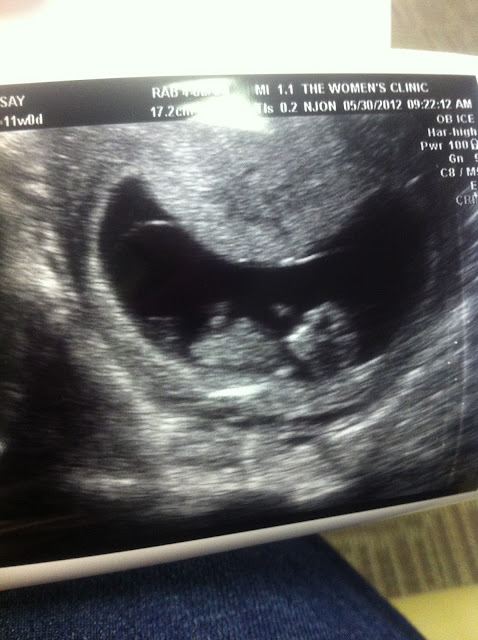

We got to visit tiny baby today.   We go back to the doctor on June 28th when, hopefully, we can do the anatomy ultrasound and learn the gender.  Until then, the new baby will be lovingly referred to as "Tiny Baby."

Tiny Baby- 11 weeks. Arms and legs and everything!

Everything went well at the doctor and we got a sneak peak at Tiny Baby, again!  Everything is looking good so far- Tiny Baby has some arms and legs and is starting to look less like a tadpole and more like a little human.

Here's a pic of Tiny Baby just 4 weeks ago-- barely a blip on the radar. (hint: the tiny white spot in the big black circle is the baby)  It's crazy how much can change in just a few short weeks.  I love you little one.